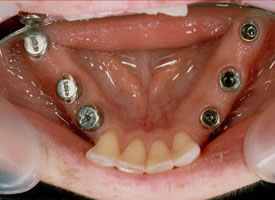

Im Unterkiefer sind bis auf die vier unteren Schneidezähne alle Seitenzähne verlorengegangen.

Auf sechs Implantaten mit jeweils zwei festsitzenden Brücken rechts und links konnten alle Zähne ersetzt werden.